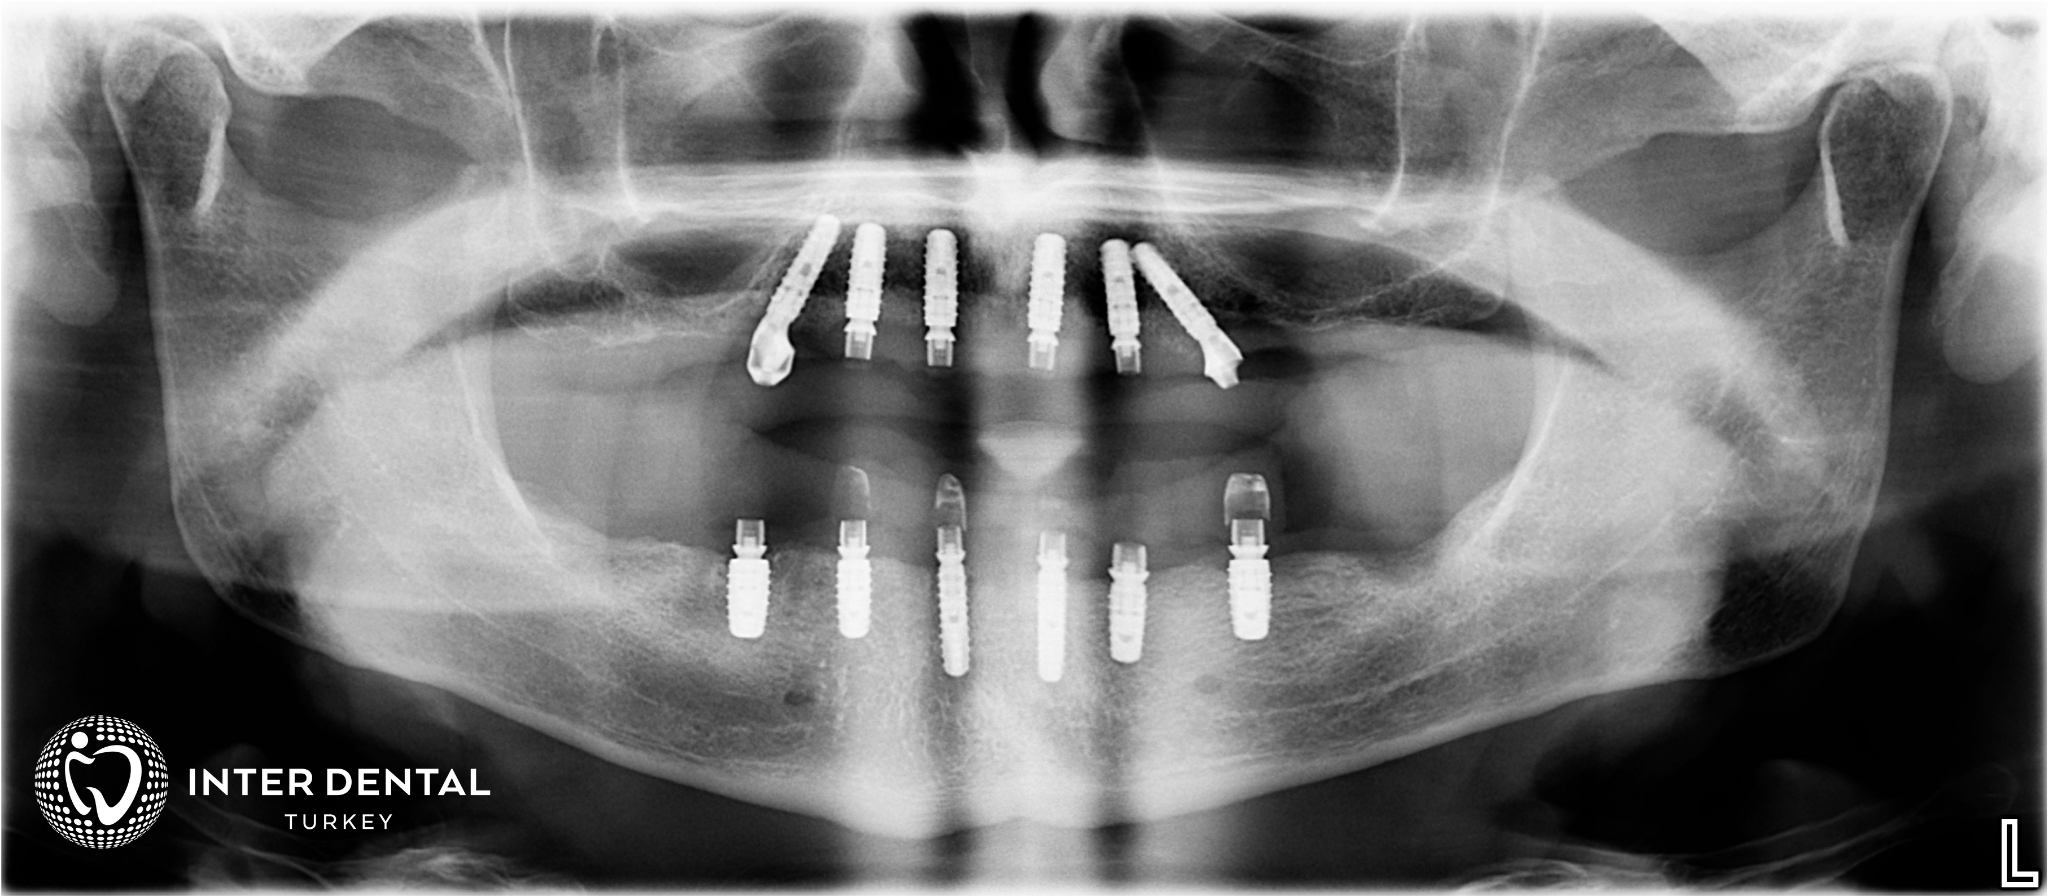

Wie Sie auf dem obigen Röntgenbild erkennen können, werden Winkel und Position jedes der 6 Implantate digital geplant und an den stärksten Punkten des Knochens platziert. Dank dieser "Surgical Guide"-Technologie (chirurgische Bohrschablonen) überlassen wir nichts dem Zufall und reduzieren das Risiko, Nebenhöhlen oder Nerven zu verletzen, auf null. Wir schließen den Prozess viel schneller und schmerzfreier ab und können oft auf aufwendige Knochenaufbau-Verfahren (Knochentransplantation) verzichten.